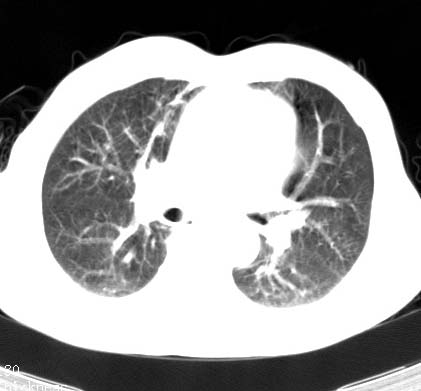

支持双上肺继发性肺结核。

tb应无悬念